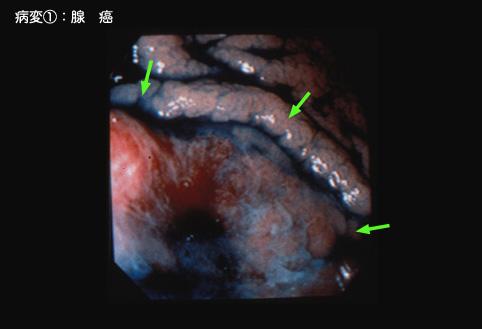

疾病(病理主体)的分类恶性上皮性肿瘤/腺癌

部位(按器官分)胃(部位)/体部

检查方法内窥镜

肿瘤的肉眼分类0型(表在型)/IIa型(IIa+IIc)

肿瘤最大直径25~29

肿瘤的深度sm